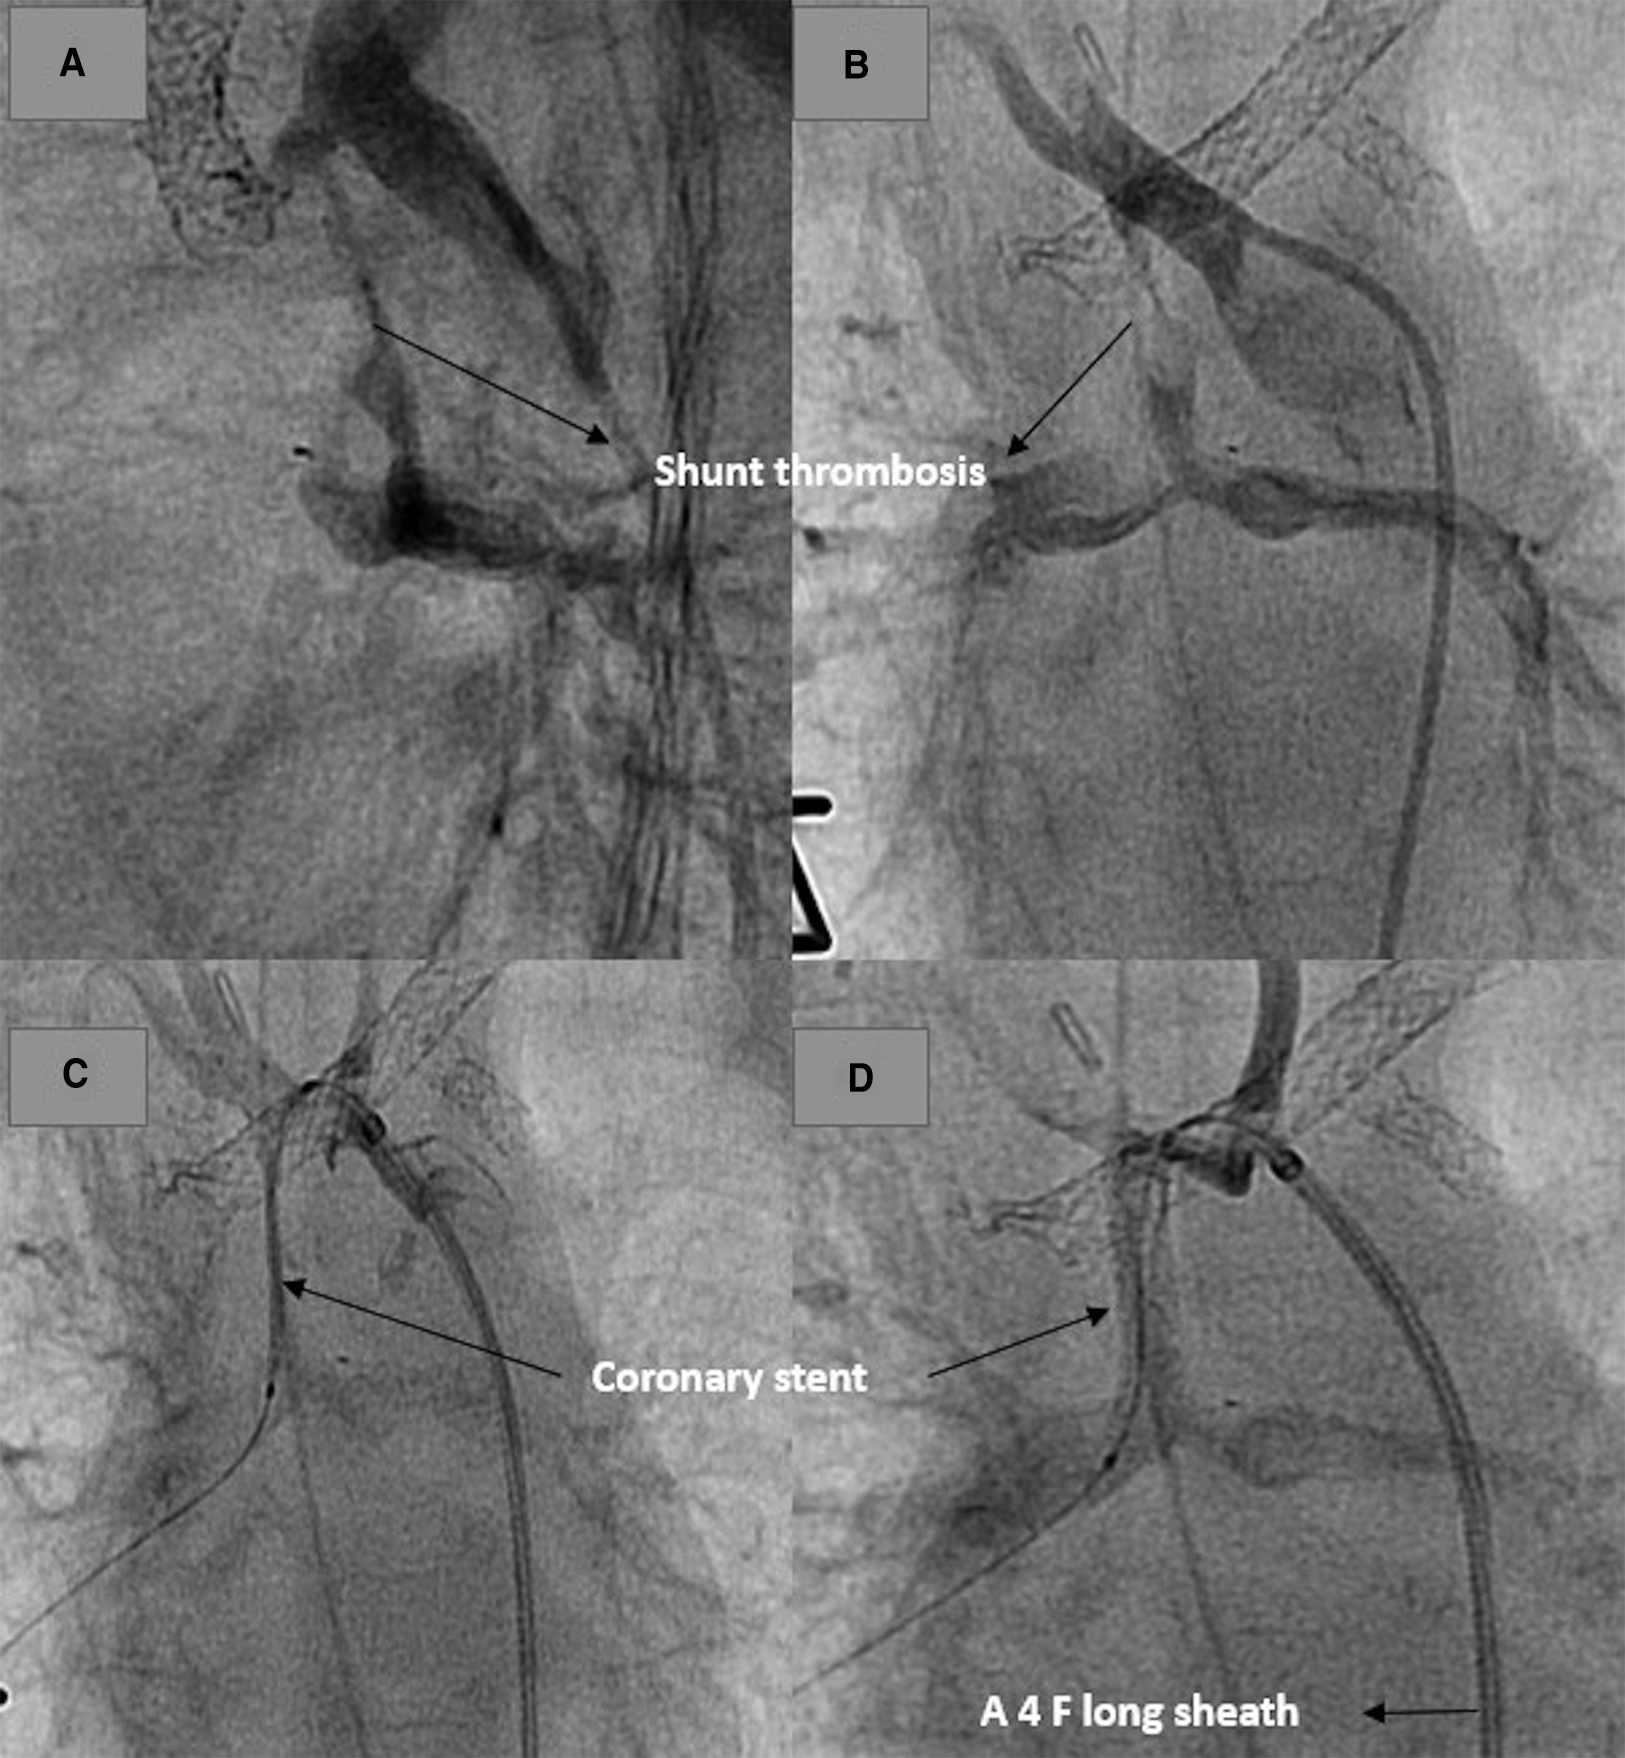

The third patient (HLHS, Norwood Palliation) had an acute shunt obstruction postoperatively and needed ECMO for survival. The interventional shunt revascularization was performed while the patient was on ECMO (Figure 6). The shunt was revised after 24 h due to an ECMO-related thrombotic event. The patient died postoperatively on ECMO.

Figure 6

Revascularization of an obstructed shunt in a patient on ECMO. (A,B) demonstrate the thrombosed shunt with the clip. (C) Stent position after recanalization of the shunt. (C) Shunt and pulmonary perfusion after stenting.